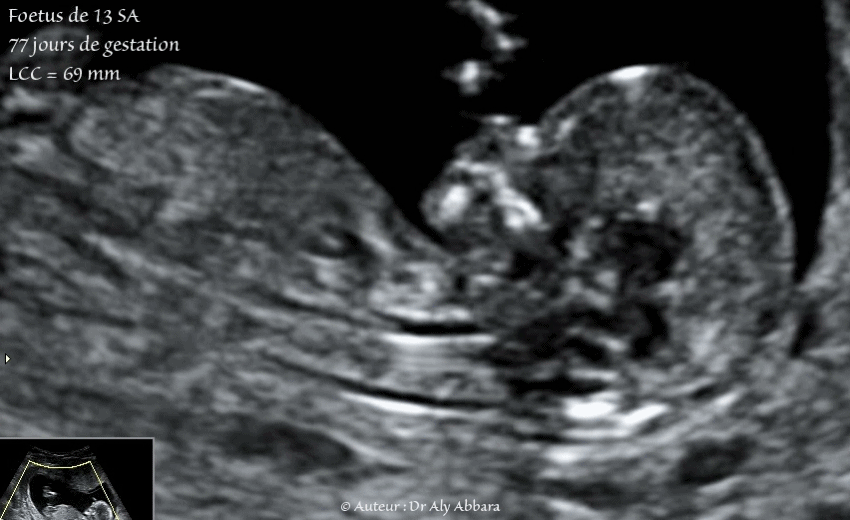

Foetus de 13 SA - anatomie et motricité :

• Vidéo et Images échographiques montrant un fœtus âgé de 77 jours de gestation (soit 13 semaines d'aménorrhée) et mettant en évidence, sur une coupe sagittale médiane puis légèrement paramédiane, le foetus est posé sur la membrane amniotique, ce qui la rend invisible sauf au moment de la déflexion de la tête où on peut identifier cette membrane derrière la nuque.

On peut également identifier les éléments anatomiques fœtaux suivants :

• le pôle céphalique avec la voûte crânienne ; le front ; l'os propre du nez ; le palais osseux, le maxillaire inférieur ;

• le cou avec au centre le trachée ;

• le tronc foetal composé de la cage thoracique ; le cœur battant ; la cavité abdominale (discrète hyperdensité intestinale physiologique à ce terme de grossesse) ;

• en arrière on identifie clairement le plan cutané sous forme d'une ligne hyperéchogène allant de la nuque jusqu'à la région dorsale

• Longueur crânio-caudale = 69 mm ; clarté nucale est mesurable = 1,9 mm.